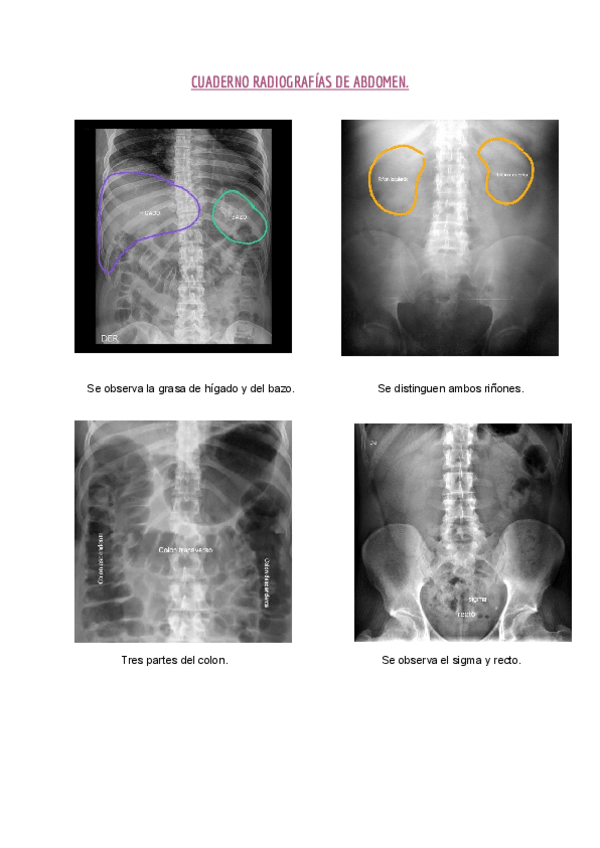

He publicado nuevos apuntes de Técnicas de Radiología Simple: Cuaderno-abdomen-HLC.pdf

3 páginas